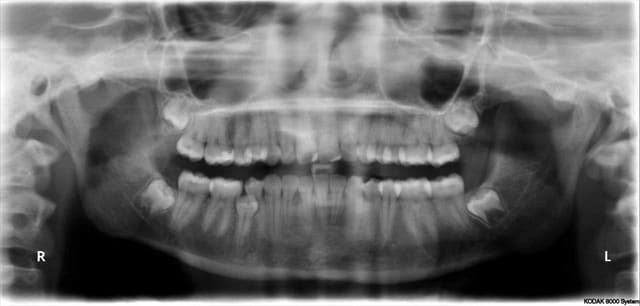

le cas montré par D57 est intéressant, magistralement exécuté, mais n'est pas forcément un cas "d'école" à suivre, bien au contraire puisque ici le choix stratégique normal aurait été de tracter la 25 et non de l'extraire...d'autant, encore une fois, que la mise en place ne posait aucune difficulté majeure...

Donc j'avais bien compris, tu as extrait 44 pour extraire 45 et ça te semble normal parce que son extraction aurait été risquée autrement. Difficile pour moi de critiquer ce choix sans avoir d'autres éléments de diagnostic que la pano. Mais je t'expose ma solution: extraire la 44 sans toucher la 45 malgré l'accés linguale et la difficulté opératoire. Sinon ne pas toucher et surveiller, voir meme espérer une éruption linguale.

Tu disais précédemment que le meilleur implant c'était la dent, en fait le meilleur implant, c'est pas d'implant.